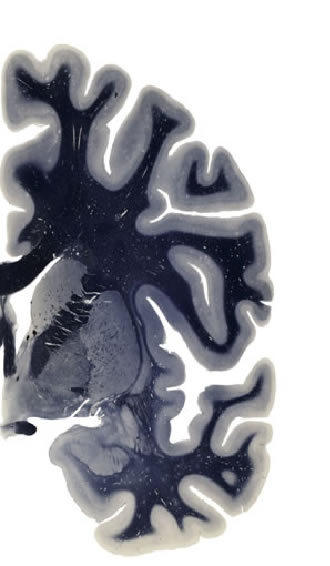

Hi-Resolution Sections · Cells (Nissl Staining) · Virtual Microscopy

Frontal sections (Nissl) from the Atlas Brain:

Slice ID:

r3-1350

Plate NR:

ca 23

Position:

1,34 mm